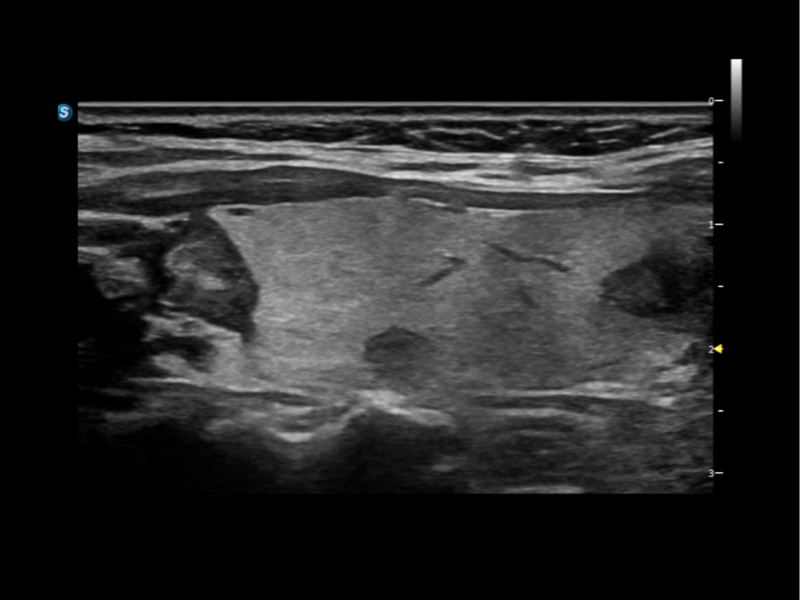

作为开立医疗全新打造的超高端旗舰超声产品,从探头抬起唤醒开启扫查到多维探头发射接收,通过先进的场成像发射、自适应聚合重建等技术,基于RF Data原始射频数据在图像生成、高端功能等方面实现突破,提供多科室综合临床解决方案。

S80 提供多样化超声成像技术,可满足不同科室的需求,在助力扫查诊断和介入治疗中发挥着重要作用。